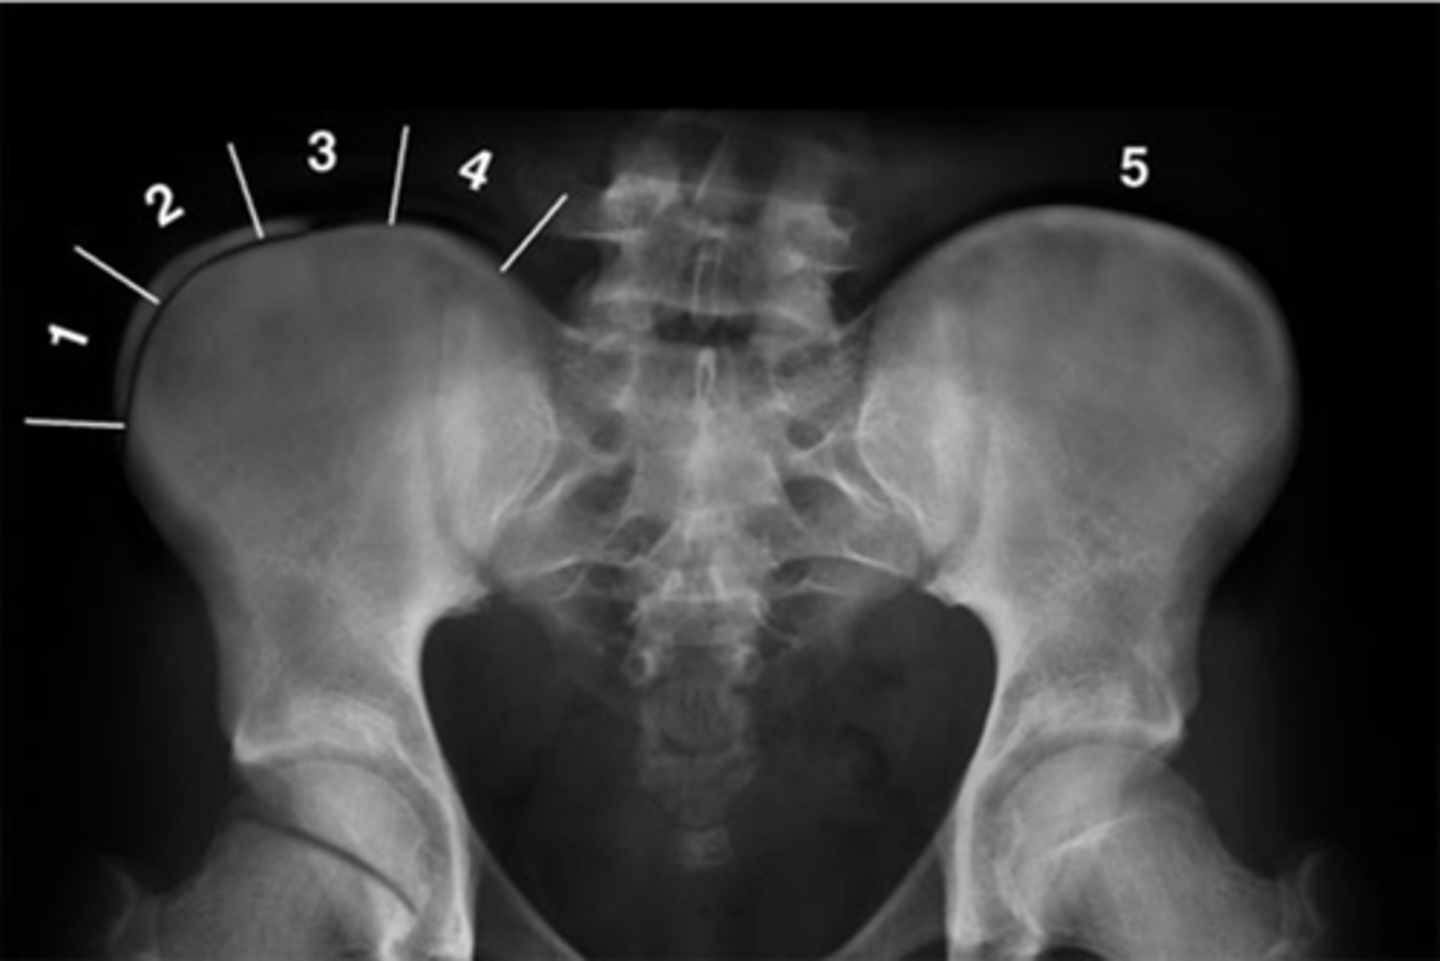

Pubic symphysis

ID 1

Left femoroacetabular joint

ID 2 (joint)

Left posterior sacroiliac joint

ID 3 (joint)

Left anterior sacroiliac joint

ID 4 (joint)

Right: gluteus medius

Left: gluteal fat stripe

ID 5

<p>ID 5</p>